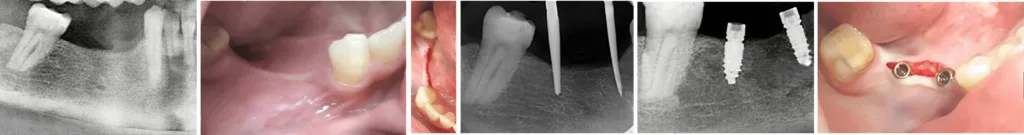

MIMI beschreibt die minimalinvasive Methodik der Implantation mithilfe der lappenlosen CNIP-Navigation (Cortical Navigated Implantation Procedure) und der Möglichkeit der ossären Metamorphose (OMM) im weichen Knochen. Die Implantatprothetik erfolgt ohne aktive Wiedereröffnung des Zahnfleisches und ohne jegliche Manipulation des Implantatkörper-Inneren, das während der Einheilzeit des zweiteiligen Systems steril bleibt (Abb. 1). Das Verfahren schont sowohl in der Chirurgie als auch in der Prothetik die den Knochen ernährende Knochenhaut und die biologische Breite. MIMI kann nicht nur bei allen Spät- und Sofortimplantaten eingesetzt werden, sondern auch als MIMI-II bei schmalen Kiefern und als MIMI-VI beim Sinuslift.

Als Navigation beim MIMI-Verfahren bedient man sich der Champions-Guides (Abb. 3), Position- und Stopp-Guides (Abb. 3) sowie der CNIP, bei der niedertourig mit etwa 30–70 U/min in der Spongiosa gebohrt und kondensiert wird. Bei dieser Tourzahl ist der Bohrer nicht in der Lage, den lateralen Kortikalisknochen zu perforieren. Selbst bei wenig Knochenangebot bzw. schmalem Kiefer kann in kürzester Zeit die MIMI-II-Technik durchgeführt werden. Dabei werden die drei Schichten – bukkale Knochenlamelle, intaktes Periost und befestigte Gingiva – um bis zu 5 mm problemlos und ohne Fraktur oder lateral-angelagerte Augmentationen nach bukkal mobilisiert. Durch das atraumatische Vorgehen wird das Aufklappen mit Lappenbildung vermieden, Periost und Mukosa werden nicht abgelöst und der „biologisch aktive Container“ bleibt erhalten (Abb. 4).

Alle Champions-Implantate sind „Made in Germany“, bestehen aus Titan Grad 4 KV mit 99% Reintitan und verfügen über ein CleanImplant Foundation Zertifikat. Sie sind vollständig digital aufgestellt und bieten ihre Implantatbibliotheken direkt für die wichtigsten CAD/CAM-Systeme wie exocad, Cerec und 3Shape an. Für einteilige Vierkantimplantate gibt es spezielle zementierbare Titan- oder Zirkon „Prep Caps“, die man zum Ausgleich größerer Achsendivergenzen oder bei Sofortimplantaten einsetzen kann. Es handelt sich dabei um „Hilfskronen“ oder „Abutments“, die nach sicherer Zementierung parallel präpariert werden können. Dank der Champions WS Condenser, die primär im „weichen Knochen“ (D3 und D4) zur Verdichtung eingesetzt werden, ist auch in diesem eine Implantatinsertion in nur wenigen Minuten und mit kurzen „Einheilzeiten“ möglich (Abb. 5). Im MIMI-Verfahren werden weder DVT noch laborgefertigte Guide-Schablonen benötigt. Insgesamt zeichnet sich das Verfahren durch seine enorme Schnelligkeit aus. Innerhalb einer Stunde und in nur zwei Patientensitzungen kann ein Einzelimplantat gesetzt werden (Abb. 7) Eine wissenschaftliche Zehnjahres-Langzeitstudie* im Auftrag des Unternehmens, in der 13.834 Implantate bei 4.192 Patienten (inklusive Rauchern und anderweitigen Risikopatienten) untersucht wurden, ergab einen 96,5-prozentigen Erfolg ohne Periimplantitis nach Albrekkson-Kriterien.